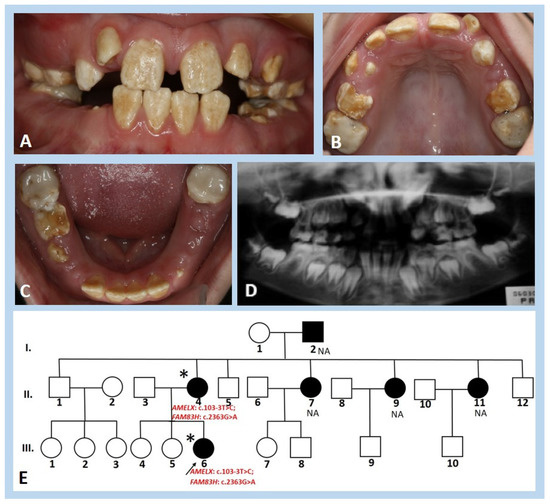

3.1. Clinical and Radiographic Findings

| Number | Family (F) | Gender | Predicted Mode of Inheritance | Phenotype * | |

|---|---|---|---|---|---|

| Hypomineralisation Type | Hypoplastic Type | ||||

| 1 | F1 | Female | ** | + | |

| 2 | F2 | Female | ** | + | |

| 3 | F3 | Male | AD | + | |

| 4 | Male | + | |||

| 5 | F4 | Male | AD | + | |

| 6 | Female | + | |||

| 7 | Female | + | |||

| 8 | Male | + | |||

| 9 | F5 | Female | ** | + | |

| 10 | F6 | Female | ** | + | |

| 11 | F7 | Female | AD | + | |

| 12 | Male | + | |||

| 13 | F8 | Male | AD | + | |

| 14 | Female | + | |||

| 15 | F9 | Female | AD | + | |

| 16 | F10 | Female | ** | + | |

| 17 | F11 | Female | AR | + | + |

| 18 | F12 | Male | AR | + | |

| 19 | F13 | Male | AD | + | + |

| 20 | Female | + | + | ||

| 21 | F14 | Female | AR | + | |

| 22 | F15 | Male | AD | + | + |

| 23 | F16 | Male | AD | + | + |

| 24 | Male | + | + | ||

| 25 | F17 | Female | AD | + | + |

| 26 | Male | + | + | ||

| 27 | F18 | Female | AR | + | |

| 28 | F19 | Female | ** | + | |

| 29 | F20 | Male | AD | + | |

| 30 | Male | + | |||

| 31 | F21 | Male | AD | + | |

| 32 | F22 | Female | ** | + | |

| 33 | F23 | Female | ** | + | |

| 34 | F24 | Male | AD | + | |

| 35 | Male | + | |||

| 36 | F25 | Female | X-linked | + | + |

| 37 | Female | + | + | ||

| 38 | F26 | Male | ** | + | |

| 39 | F27 | Female | X-linked | + | + |

| 40 | F28 | Female | ** | + | |